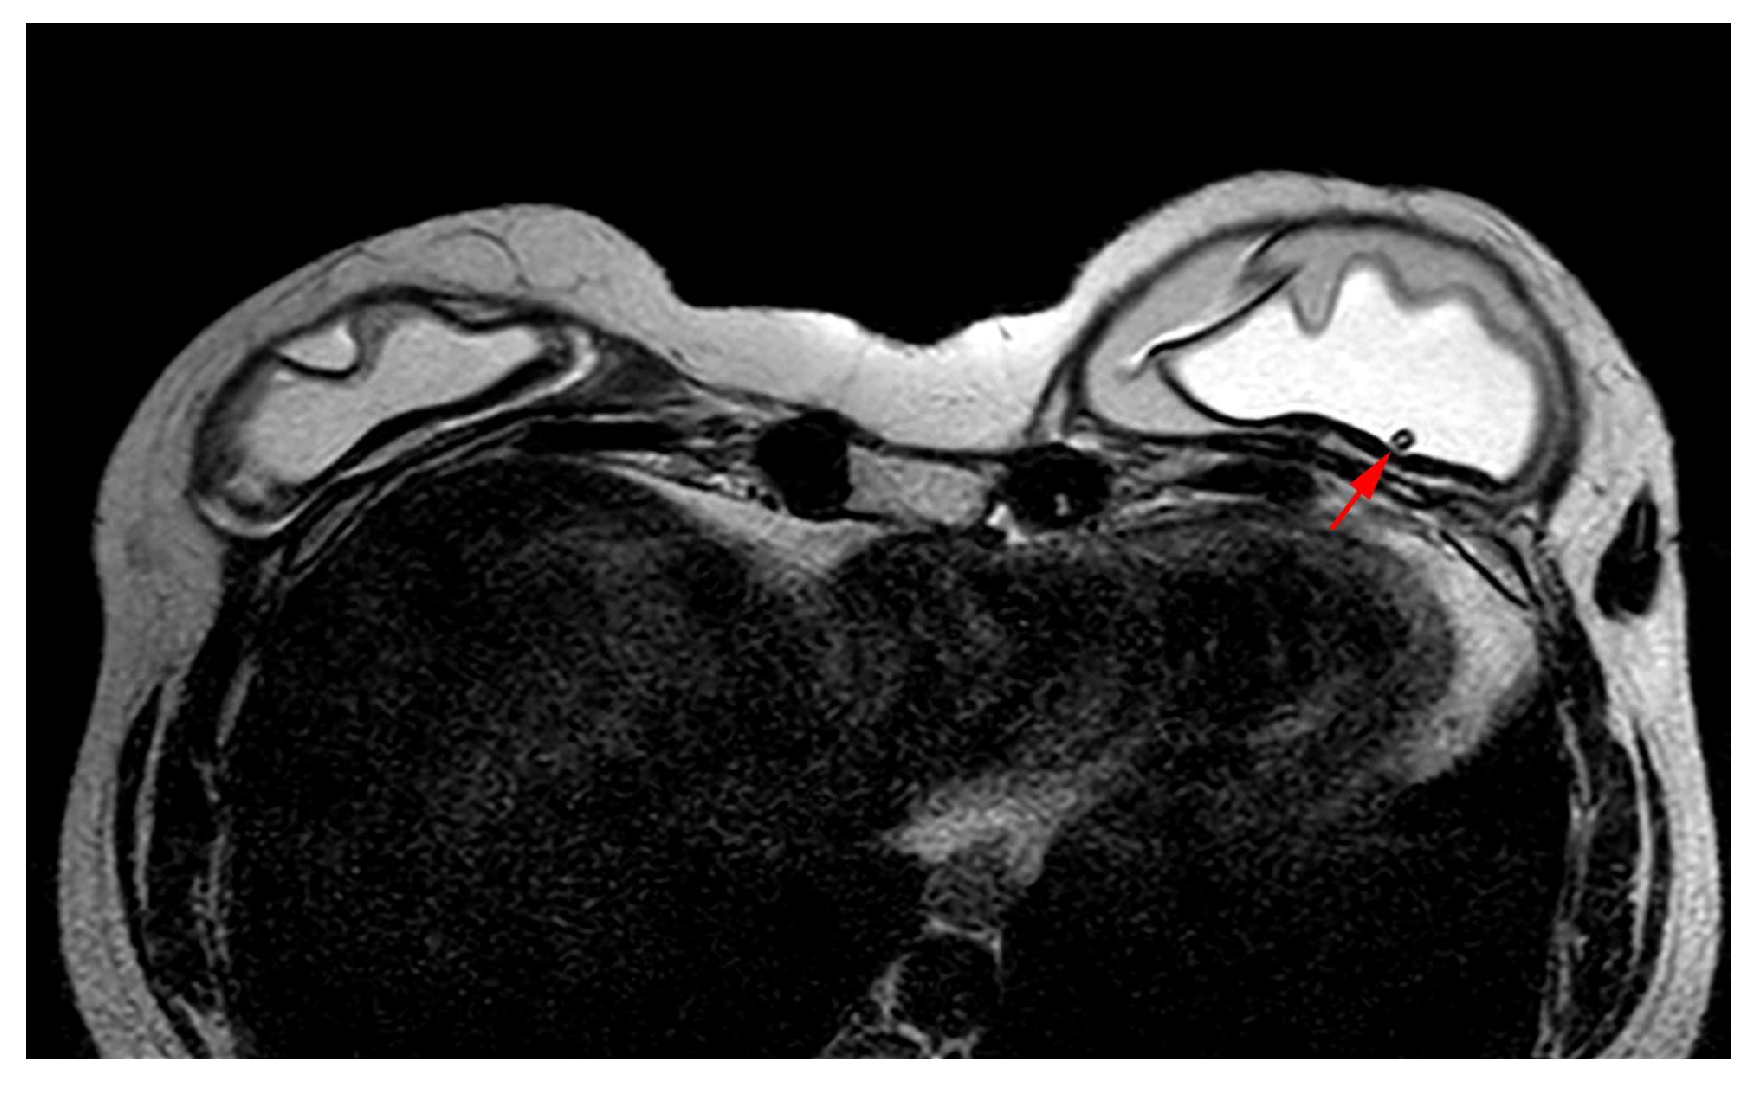

5.2.6. Breast Implant Associated Atypical Large Cell Lymphoma (BIA-ALCL)

- Sharma, B.; Jurgensen-Rauch, A.; Pace, E.; Attygalle, A.D.; Sharma, R.; Bommier, C.; Wotherspoon, A.C.; Sharma, S.; Iyengar, S.; El-Sharkawi, D. Breast Implant-associated Anaplastic Large Cell Lymphoma: Review and Multiparametric Imaging Paradigms. Radiographics 2020, 40, 609–628. [Google Scholar] [CrossRef] [PubMed]

- Adrada, B.E.; Miranda, R.N.; Rauch, G.M.; Arribas, E.; Kanagal-Shamanna, R.; Clemens, M.W.; Fanale, M.; Haideri, N.; Mustafa, E.; Larrinaga, J.; et al. Breast implant-associated anaplastic large cell lymphoma: Sensitivity, specificity, and findings of imaging studies in 44 patients. Breast Cancer Res. Treat. 2014, 147, 1–14. [Google Scholar] [CrossRef] [PubMed]

- Rotili, A.; Ferrari, F.; Nicosia, L.; Pesapane, F.; Tabanelli, V.; Fiori, S.; Vanazzi, A.; Meneghetti, L.; Abbate, F.; Latronico, A.; et al. MRI features of breast implant-associated anaplastic large cell lymphoma. Br. J. Radiol. 2021, 94, 20210093. [Google Scholar] [CrossRef]